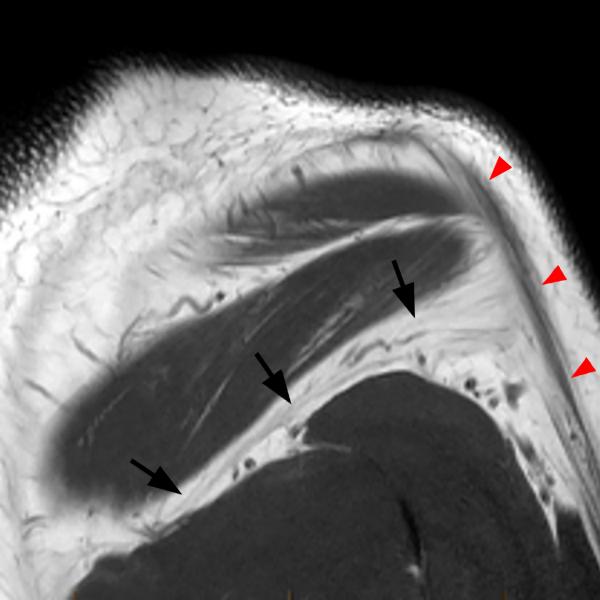

Shoulder Cysts Mri

From mavink.com

Shoulder Cysts Mri Back Shoulder Cyst A paralabral cyst, or ganglion cyst, is a fluid collection arising from the shoulder’s ball and socket joint. Let’s start by looking at the four most common causes of a lump on the back of your shoulder and how to treat them. A sebaceous cyst on the shoulder, aka epidermoid shoulder cyst is a small sac filled with keratin, a. Back Shoulder Cyst.